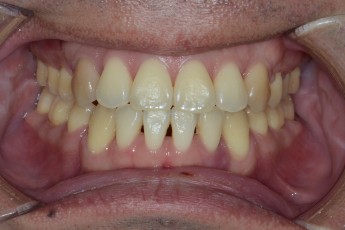

BEFORE & AFTER